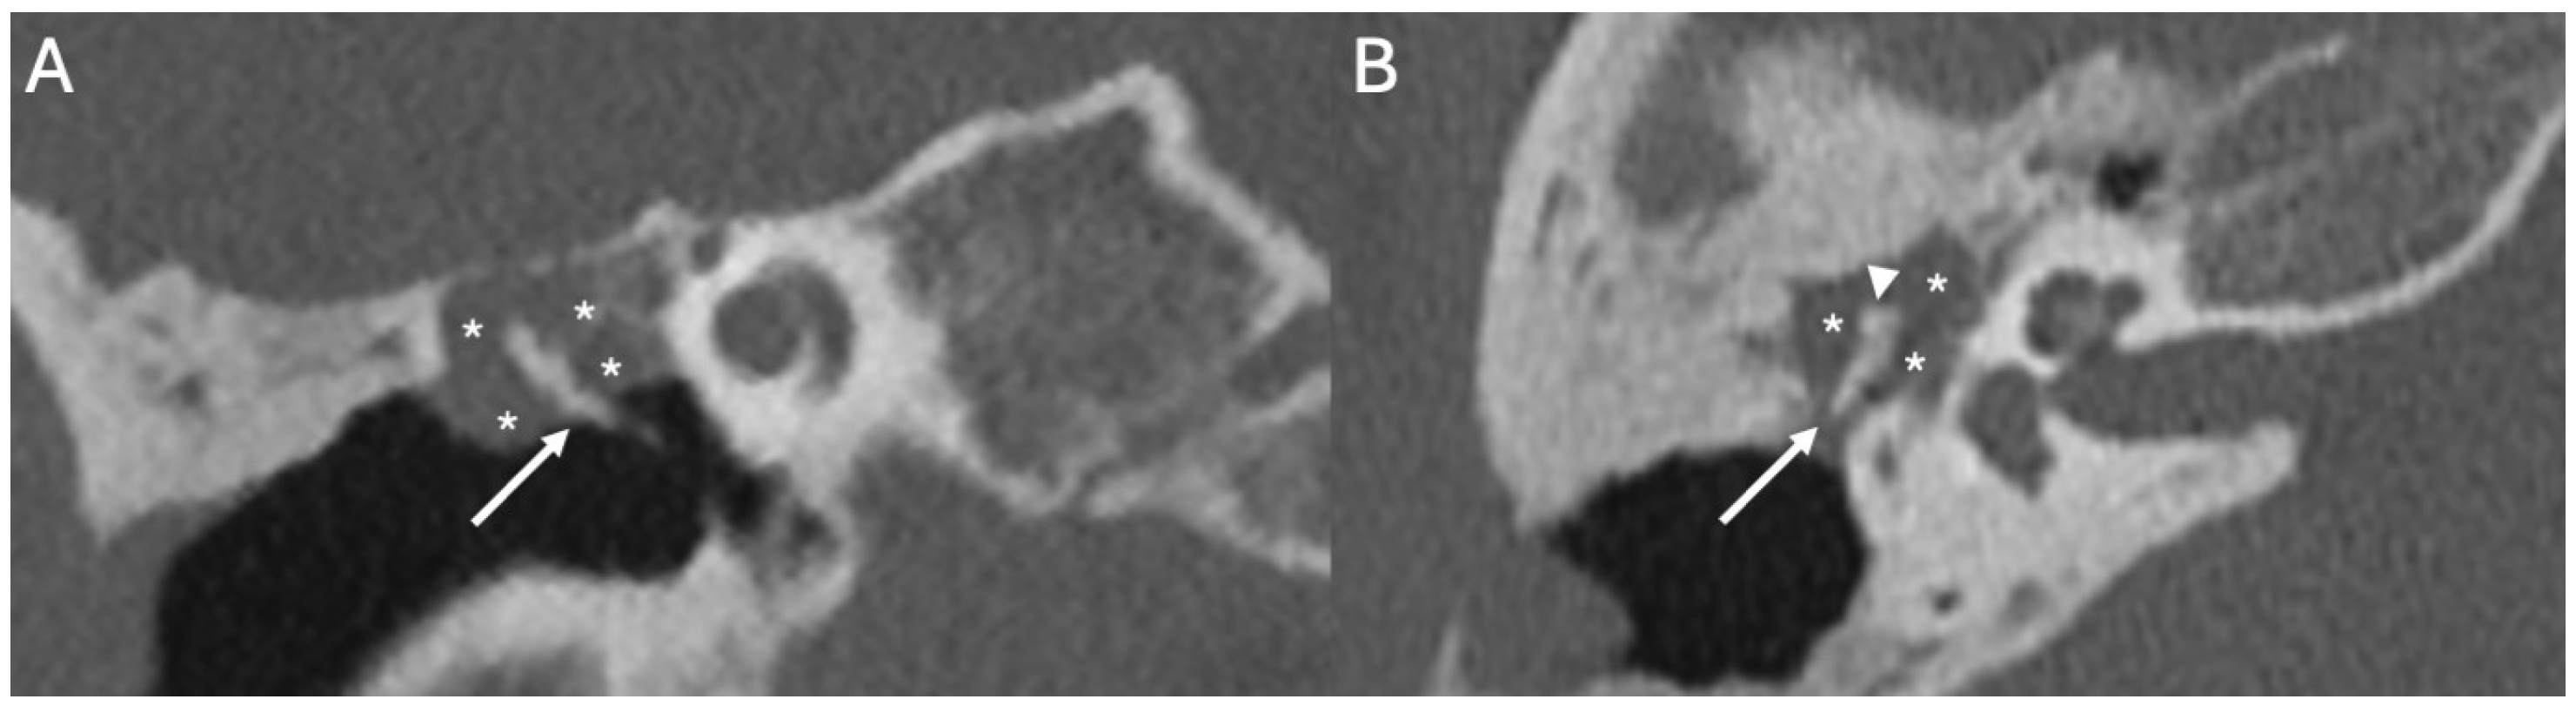

3.2. Bony Dehiscence

| Bony Dehiscence/Temporal Bone Defects | Barbara et al., 2022 [22]; Sanna et al., 2009 [23]; Lim et al., 2012 [24]; Rabiei et al., 2025 [25] | Case-based studies and reviews | Tegmen tympani or semicircular canal defects create a route for meningitis and meningoencephalocele; HRCT coronal reconstructions preferred. |